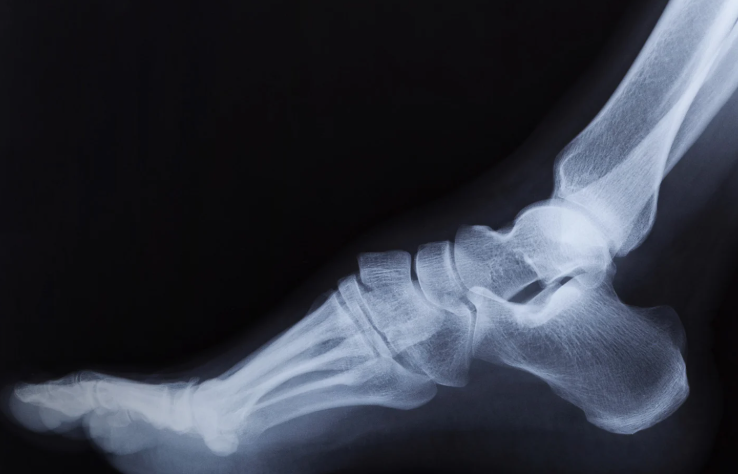

Do I Need an MRI or X-Ray?

Not always. Most ankle instability can be diagnosed clinically during physiotherapy assessment. Imaging is only recommended if:

- There is severe swelling or bruising

- Pain persists longer than expected

- There is suspicion of fracture or significant tearing

- You’re not responding to treatment